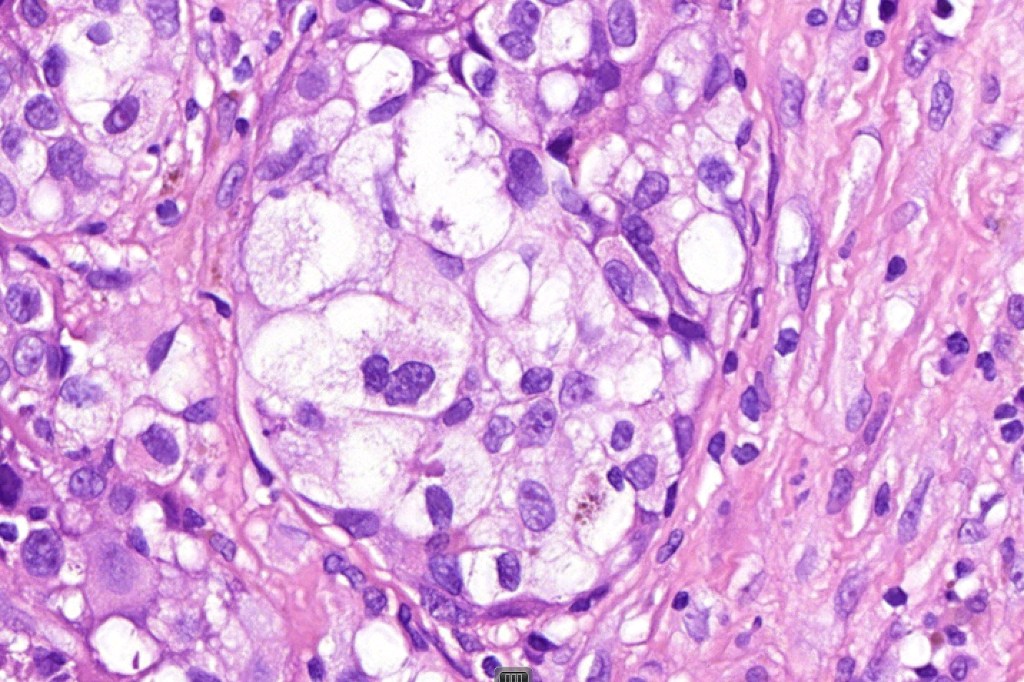

These are very rare variants of amelanotic or virtually amelanotic melanoma where a primary melanoma or a metastasis shows partial (DN) or complete loss (UN) of recognizable histological and immunohistochemical features. The histology may lead the pathologists to consider lymphoma, sarcoma, anaplastic carcinoma or a small cell tumor. Some examples of rhabdoid melanoma & melanoma with heterologous differentiation probably belong in this category. Ultimately, if there is no identifiable/recognizable primary tumor, diagnosis may only be comfortably made with next-generation sequencing. In the cases presented below, immunohistochemistry was of value in determining the melanoctic nature of the tumor (undifferentiated melanoma).